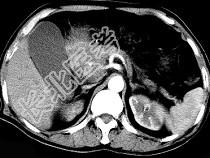

- 单项选择题男,50岁, 黄疸进行性加重、腹部胀痛不适、食欲减退、体重减轻、上腹部可触及肿块,CT如图, 最可能的诊断是 ( )

A、胰头癌

B、转移瘤

C、慢性胰腺炎

D、急性胰腺炎

E、腹膜后淋巴瘤